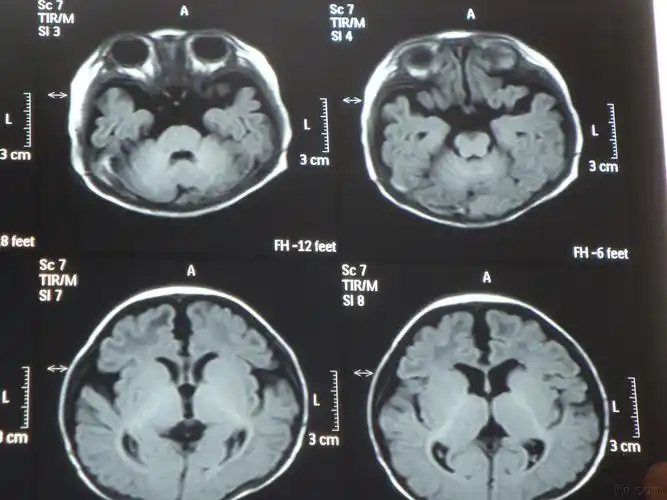

出生两个月小儿脑萎缩